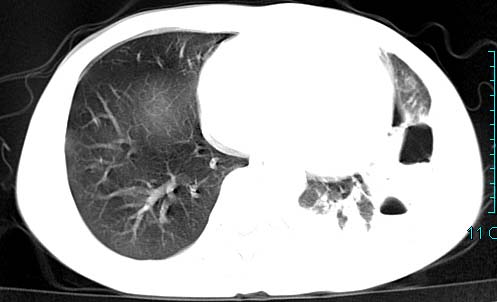

以下是引用qian在2006-3-28 14:32:00的发言:[br]左肺下叶大片状阴影,密度不均,见有条片影和空洞及气液平,少量胸腔积液伴有胸膜增厚,从图像看积液密度比水的密度高,结合病史,考虑左下肺化脓性炎症伴有脓胸。

以下是引用wawaquan在2006-3-28 22:25:00的发言:[br]左上肺舌段多发斑片影。结合“男24y咳嗽咳痰气促伴高热(38.5--39.5)20多天”及穿刺史,[br]考虑1 左下肺化脓性炎症;2脓胸。

以下是引用乡医在2006-3-28 18:37:00的发言:[br]左侧多发液气平面结合患者男24y咳嗽咳痰气促伴高热(38.5--39.5)20多天,查胸水:ldh239.3,总蛋白59.19,tb-ab阴性,利凡它试验+,红c2.7*109,白c1.08*109,分类淋巴92%分叶8%,考虑1脓胸2肺隔离征感染